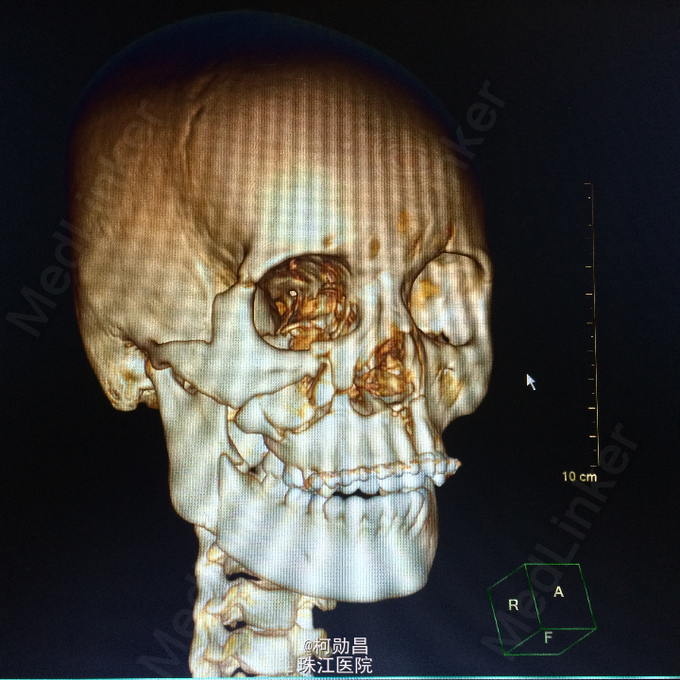

查体:脑膜刺激征阳性 辅助检查:复查头颅CT及三维颅骨重建提示:血肿较前吸收,颅骨多发骨折,左额部较为明显

诊断:重型颅脑损伤,脑脊液耳漏、颅骨多发骨折